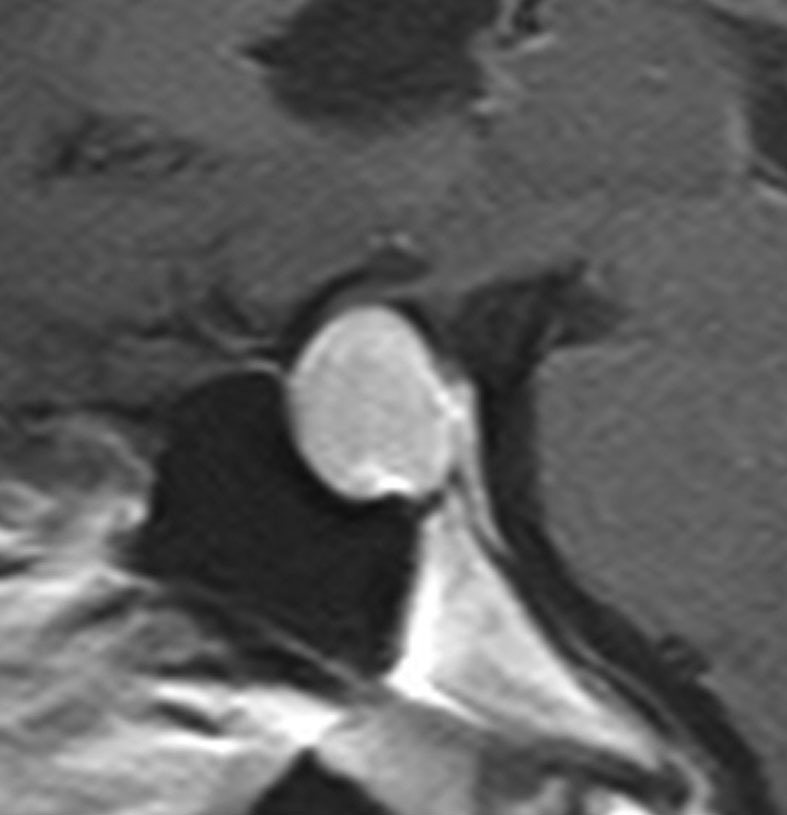

とても小さな腫瘍(微小腺腫) microadenoma

1cm以下の小さなものを微小腺腫といいます。ホルモンを異常に分泌する腫瘍は摘出する必要がありますが,そうでないものは治療の必要がありません。微小腺腫を数年観察しても増大する確率は10%くらいです。逆に,それ以上に大きなものだと,50%くらいの確率で増大します。

日本で汎用されているものでは最も解像力が高い3テスラMRIで撮影された,ガドリニウム増強像です。左側の画像では下垂体の大きさと形は正常に見えます。画像を調整すると,下垂体の内部,右端(黄色の矢印の先)に6mmくらいの小さな腺腫がみつかりました。MRIの性能がよくなったことによって数mmの小さなものも診断できるようになりました。